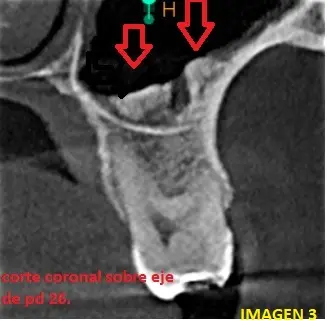

En el corte coronal, podemos observar imágenes de densidad cálcica a nivel del piso del seno maxilar (flechas rojas) con densidad semejante al hueso y que parecen estar fusionadas con el piso del seno maxilar. (ver Imagen 3)